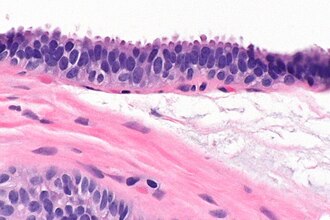

Columnar cell change of the breast - very high magnification. H&E stain. (WC/Nephron)

• Secretory cells (line gland lumen) have columnar morphology.

• May have "apical snouts".

• Blebs or round balls eosinophilic material appear to be adjacent to the cell at their luminal surface.

• The snouts are attached to the cell-- appear as round ball only in the plane of section.

• Cytoplasm +/-eosinophilia.

• Often (purple) luminal calcifications.